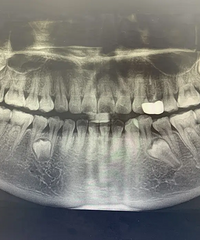

拔除十二颗智齿什么感觉?

转自豆瓣,12颗智齿,这真的是刷新了我的认知。。。。。。直接上图,有12颗智齿在嘴巴里是一种什么样的感觉啊,我有2颗阻生牙,其中一颗上火了都会发炎